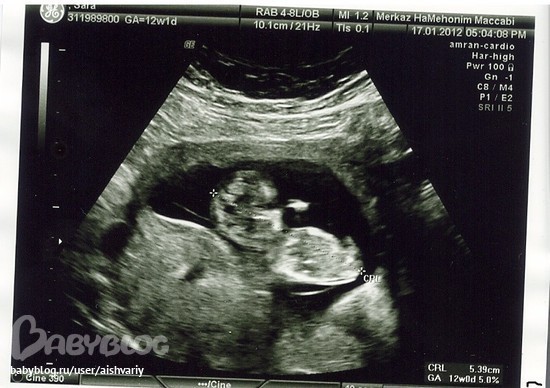

Сделали скрининговое УЗИ!

Результаты: УЗИ, КТГ, доплера, скринингаВ вторник сходили с мужем на скрининговое узи. врач проверил измерил, сказал что всё у нашей бусикки хорошо, пол пока не сказал , ножками ребёночек прикрывался, но это не страшно через 3 недели у нас ещё один паход к узисту. может тогда и скажут. А теперь фоотки нашей бусинки.